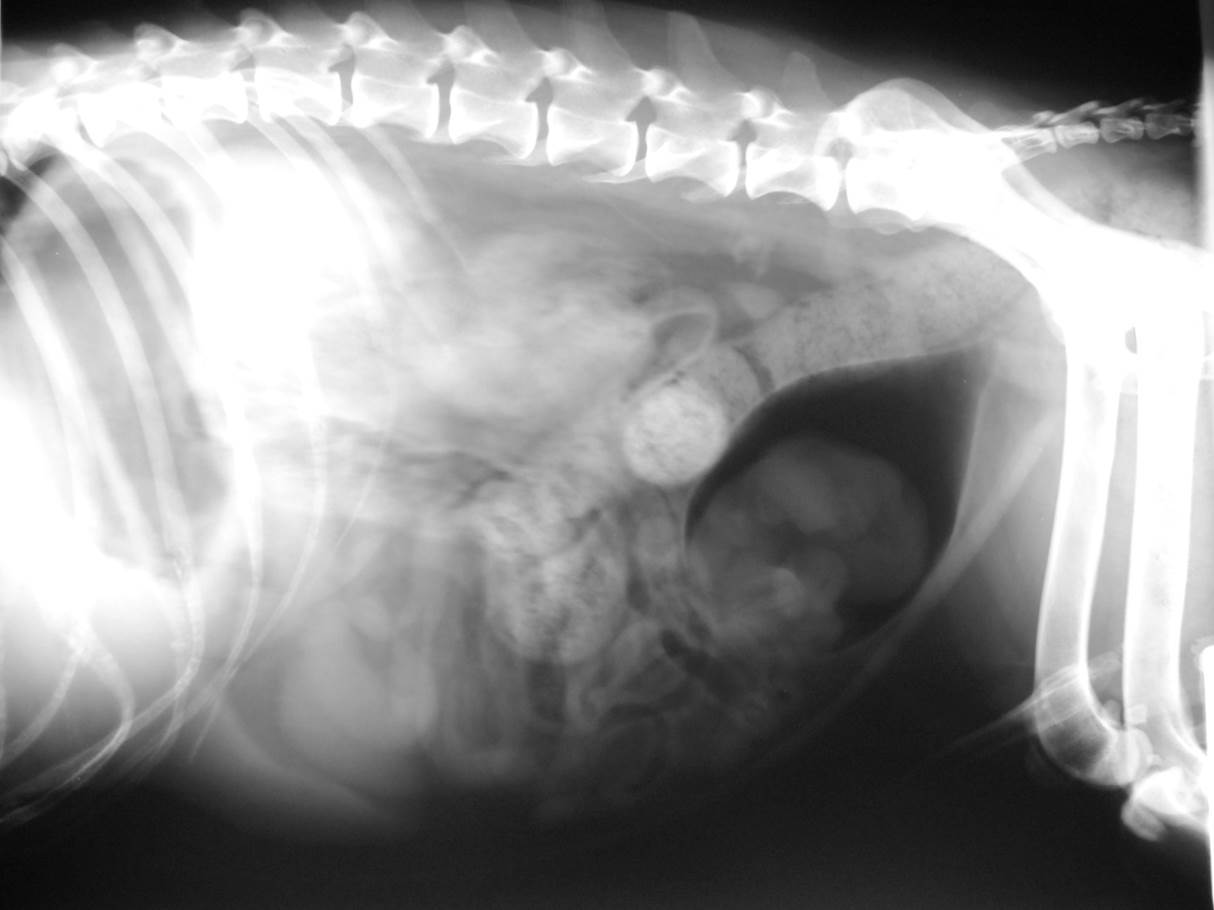

Case Joss

Discuss this case?

–catheter biopsy hopefully to confirm a benign/inflammatory lesion

–focus on identifying a UTI and managing with a prolonged course of antibiotics (?6-8 weeks minimum)

–surgical curettage of the bladder

What is Polypoid cystitis?

Polypoid cystitis is a rare disease of the urinary bladder in dogs characterized by inflammation, epithelial proliferation, and development of a polypoid mass or masses without histopathologic evidence of neoplasia.

What bacteria are/have been isolated in polypoid cystitis?

Proteus spp were the most common bacterial isolates (12/52 or 23.1%) identified when all urine samples obtained for culture at any time during the course study were considered. Other commonly isolated organisms included Escherichia coli , Staphylococcus spp, and Enterococcus spp. Several dogs (7/17) also had cystic calculi at some time during the course of their disease.

Where are most of the masses found in polypoid cystitis?

Most of the masses (11/14) were located cranioventrally in the bladder as opposed to transitional cell carcinoma, which has a predilection for the bladder neck or trigone area. It is unknown whether persistent or recurrent UTI predisposes to polyp formation or if polyps predispose to UTI.

What is the treatment for polypoid cystitis?

Surgery and removal of all polyps was the most efficacious treatment in dogs of this study. The question of whether or not polyps represent preneoplastic lesions remains unanswered and constitutes an area for future investigation